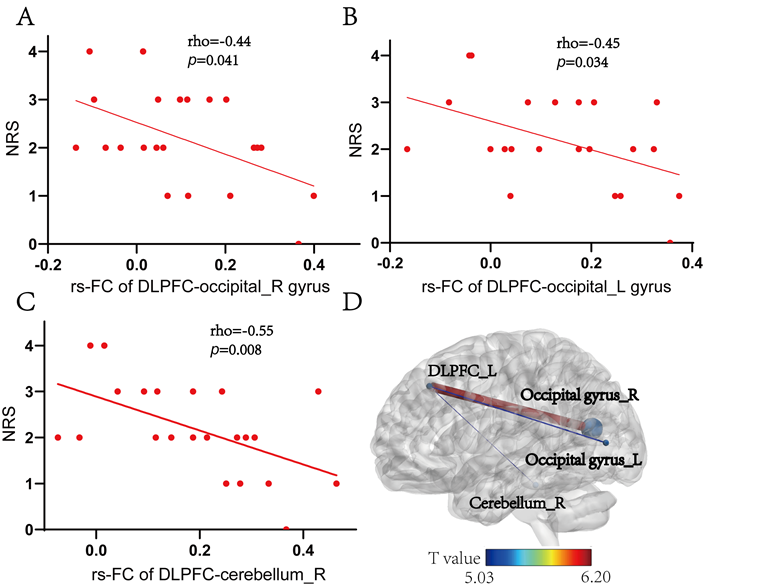

研究结果表明,相较于对照组,实验组干预后疼痛(NRS评分)改善更明显,恐惧回避情况(FABQ)也得到明显改善。干预后实验组左侧DLPFC与右侧小脑及双侧枕回之间的功能连接显著增强(图1)。相关性分析表明,NRS得分与左侧DLPFC和右侧小脑、双侧枕叶回的功能连接之间存在显著负相关(图2)。本研究提示iTBS可能通过强化DLPFC-小脑-枕回环路的功能连接,增强疼痛抑制与认知调控,从而缓解慢性腰痛症状。

图2. 实验组临床疼痛评分与脑功能连接的相关性分析